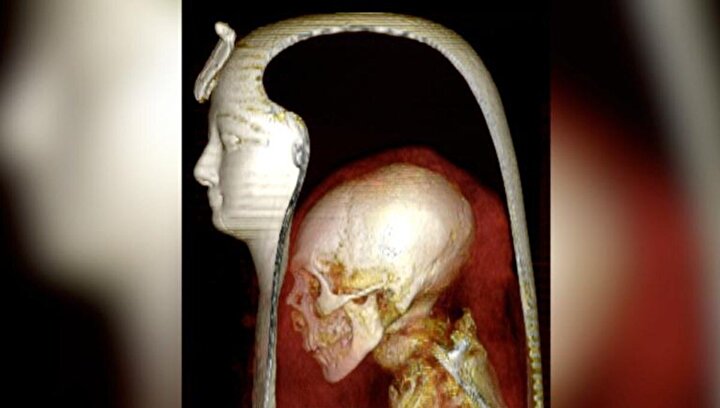

NTV'de yer alan habere göre, Mısırlı bilim insanları 3 bin 500 yıllık mumyanın sargılarını açmak ve içeriğini incelemek için üç boyutlu bilgisayarlı tomografi (BT) taramasını kullandı.

Kahire Üniversitesi Tıp Fakültesi'nde radyoloji uzmanı olan Prof. Dr. Sahar Saleem konuya ilişkin yaptığı açıklamada, "Mumyayı dijital olarak açarak ve sanal katmanlarını (yüz maskesini, bandajları ve mumyanın kendisini) 'soyarak' bu iyi korunmuş firavunu benzeri görülmemiş ayrıntılarla incelme olanağı bulduk" dedi.

Frontiers in Medicine dergisinde yayımlanan çalışmanın bulguları, I. Amenhotep’in öldüğünde yaklaşık 35 yaşında ve 169 santimetre boyunda olduğunu buldu. Ayrıca firavunun sünnetli olduğu ve sağlıklı dişleri olduğu ortaya konuldu. Uzmanlar, ayrıca sargıların içinde yaklaşık 30 muskayı ve benzersiz bir altın kuşağı ortaya çıktı.

Diğer taraftan Saleem; firavunun dar bir çenesi, küçük bir burnu, kıvırcık saçları ve hafif çıkıntılı üst dişleri olduğunu söyledi. Çalışmanını, ölüm nedenini açıklayacak herhangi bir yara veya şekil bozukluğunu göstermediğini aktardı.